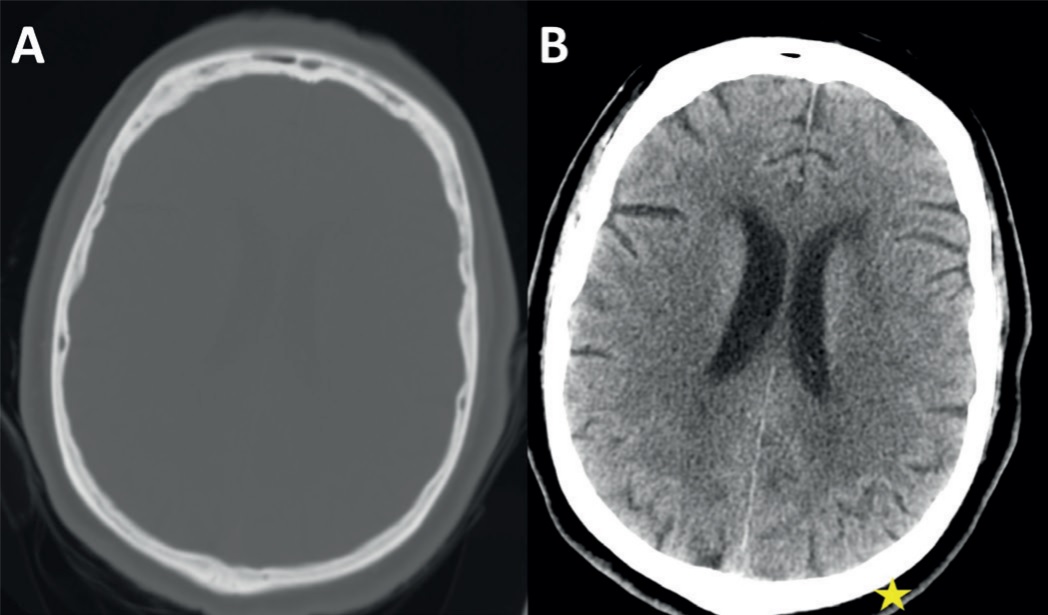

The radiologists perform a task named “windowing and leveling” which means they set the window “level” and window “width”. An example is depicted in Figure 2.3. The "window level” is the HU value for representing mid-grays. The “width” is the range of gray values where everything larger or smaller than the "width" is displayed in black or white.

Current methods for visualization of medical data include the conventional viewing of the volumetric data which is a slice-by-slice viewing method for axial, sagittal and coronal imaging planes or sometimes oblique reformats [67], as shown in Figure 2.4.